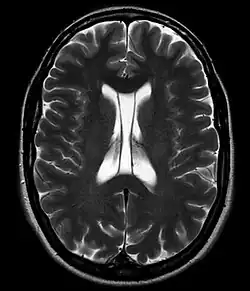

Cavum septi pellucidi

Als Cavum septi pellucidi (auch Septum-pellucidum-Zyste, Pseudoventrikel, fünfter Ventrikel, Duncans Ventrikel, Sylvischer Ventrikel, Vieussens’ Ventrikel, Wenzels Ventrikel und weitere) bezeichnet man den Hohlraum zwischen den Blättern des Septum pellucidum zwischen den Vorderhörnern der Seitenventrikel des Gehirns. Wenn eine Ausdehnung nach dorsal hinter das Foramen Monroi vorliegt, spricht man von einem Cavum vergae, wobei es sich nicht um eine andere anatomische Struktur handelt.

Der Hohlraum beinhaltet in der Regel normalen Liquor. Eine Kommunikation mit den anderen Liquorräumen kann, muss aber nicht vorhanden sein. Als Zufallsbefund beim Erwachsenen in der Computertomographie oder Kernspintomographie gefunden, ist das Cavum meist nur wenige Millimeter groß. Auch größere Befunde machen selten Probleme. In Einzelfällen kommt es zu einer Kompression des Foramen Monroi mit Ausbildung eines Hydrozephalus. In diesen Fällen ist eine neurochirurgische Behandlung zur Dekompression notwendig.